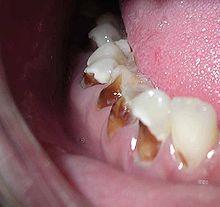

Another pattern of decay is "rampant caries", which signifies advanced or severe decay on multiple surfaces of many teeth.[96] Rampant caries may be seen in individuals with xerostomia, poor oral hygiene, stimulant use (due to drug-induced dry mouth[97]), and/or large sugar intake. If rampant caries is a result of previous radiation to the head and neck, it may be described as radiation-induced caries. Problems can also be caused by the self-destruction of roots and whole tooth resorption when new teeth erupt or later from unknown causes.

Early childhood caries

Early childhood caries (ECC), also known as "baby bottle caries," "baby bottle tooth decay" or "bottle rot," is a pattern of decay found in young children with their deciduous (baby) teeth. This must include the presence of at least one carious lesion on a primary tooth in a child under the age of 6 years.[93] The teeth most likely affected are the maxillary anterior teeth, but all teeth can be affected.[94] The name for this type of caries comes from the fact that the decay usually is a result of allowing children to fall asleep with sweetened liquids in their bottles or feeding children sweetened liquids multiple times during the day.[95]